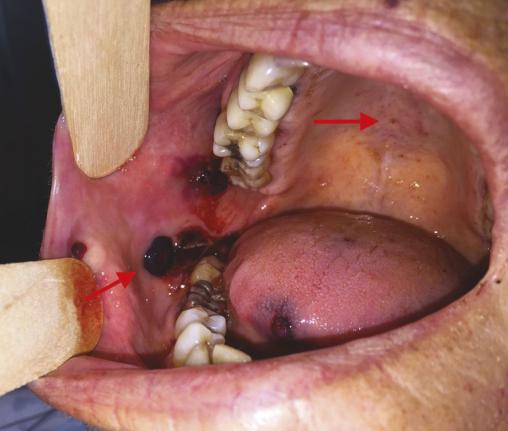

Cette femme de 77 ans, traitée pour une hypertension artérielle, se présentait aux urgences odontologiques à la suite de l’apparition en 24 heures de lésions intrabuccales extensives. L’anamnèse notait une épistaxis unilatérale associée à un flou visuel sans altération de l’état général ou modification récente de son traitement. L’examen endobuccal notait la présence de bulles hémorragiques et des pétéchies intrabuccales (fig. 1). L’examen exobuccal notait un purpura extensif des membres inférieurs (fig. 2) associé à des ecchymoses au niveau des cuisses et du tronc, réalisant un syndrome hémorragique avec signes de gravité. L’hémogramme montrait une thrombopénie sévère isolée (5 000/mm3), faisant suspecter le diagnostic de purpura thrombopénique immunologique, confirmé par la normalité du myélogramme et du bilan immun.